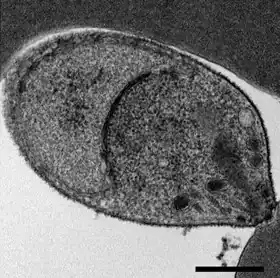

Der Lebenszyklus von P. knowlesi gleicht im Wesentlichen dem anderer Plasmodien. Der Parasit zeigt einen obligaten Wirtswechsel. Die Sporozoiten gelangen durch infizierte Stechmücken in die Blutbahn des Affen oder Menschen, wandern von dort in die Leber und dringen in Hepatozyten ein, in denen sie sich ungeschlechtlich vermehren. Die Inkubationszeit dieser Leberphase beträgt bei Affen nur fünf bis sechs Tage.

Die Leberschizonten produzieren Merozoiten, die freigesetzt werden und Erythrozyten befallen, wo eine weitere ungeschlechtliche Vermehrung stattfindet. Die Generationszeit bei der Vermehrung in den Erythrozyten beträgt ungefähr 24 Stunden und ist damit kürzer als bei allen anderen Malariaerregern der Primaten. Durch eine Synchronisierung der Entwicklung kommt es am Ende jedes Vermehrungszyklus zu einer massenhaften Freisetzung neuer Parasiten, die mit einem täglichen Fieberschub verbunden ist.